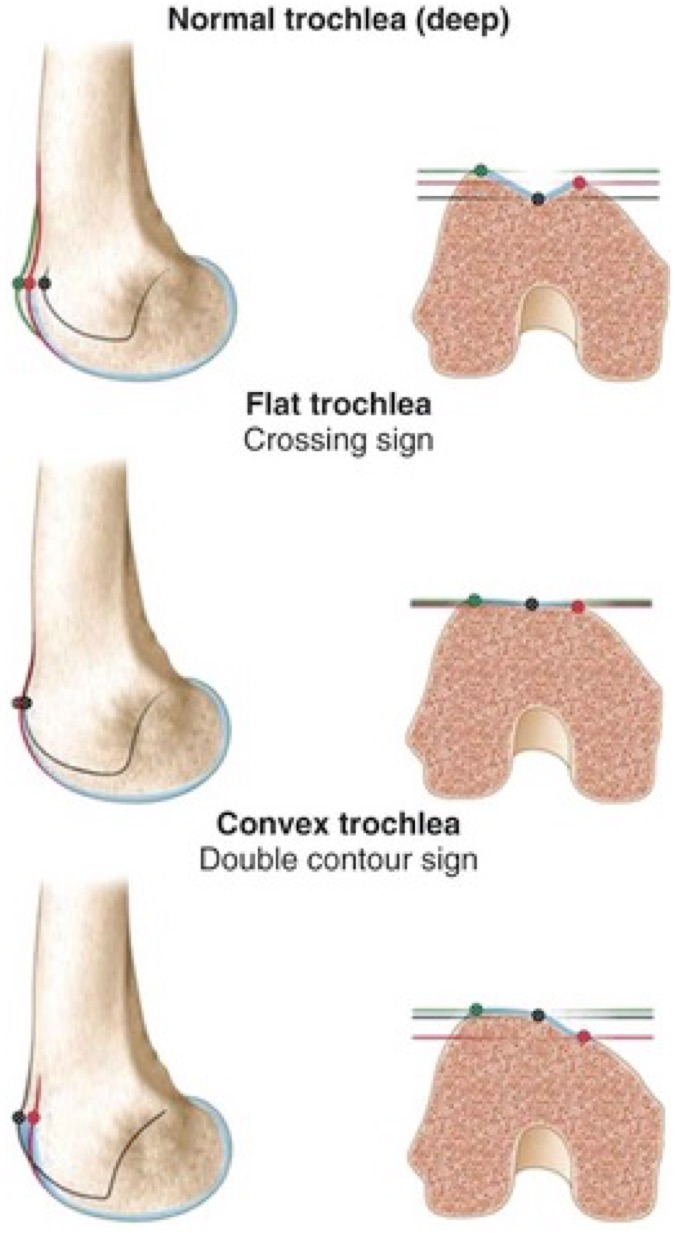

Plantar Fasciitis Foot Ankle Orthobullets outlet, Plantar Fasciitis Foot Ankle Orthobullets outlet, Achilles Tendonitis Foot Ankle Orthobullets outlet, Plantar Fasciitis Foot Ankle Orthobullets outlet, Plantar Fasciitis Orthopedics Medbullets Step 2 3 outlet, Achilles Tendonitis Foot Ankle Orthobullets outlet, Plantar Fasciitis Orthopedics Medbullets Step 2 3 outlet, Plantar Fasciitis Foot Ankle Orthobullets outlet, Calcaneus Fractures Trauma Orthobullets outlet, Orthotics Foot Ankle Orthobullets outlet, Orthobullets An example of a varus foot that corrects to slight outlet, Heel Pain and plantar fascitis Everything You Need To Know Dr. Nabil Ebraheim outlet, Calcaneus Fractures Trauma Orthobullets outlet, Ortho Dx Suspected Plantar Fasciitis Clinical Advisor outlet, Orthotics Foot Ankle Orthobullets outlet, Orthobullets A lateral radiograph of the ankle demonstrating outlet, Ankle Arthritis Foot Ankle Orthobullets outlet, Ankle Arthritis Foot Ankle Orthobullets outlet, Haglund s Deformity and Other Causes of Heel Pain in Runners iRunFar outlet, Midfoot Arthritis Foot Ankle Orthobullets outlet, Ankle Fractures Trauma Orthobullets outlet, Ankle Arthritis Foot Ankle Orthobullets outlet, Question 289 Qbank Orthobullets outlet, Baxter s Nerve Entrapment Heel Pain Treatment Melbourne outlet, Orthobullets Orthobullets added a new photo outlet, Orthotics Foot Ankle Orthobullets outlet, Ankle Arthritis Foot Ankle Orthobullets outlet, Mid Foot Osteoarthritis Causes Symptoms Treatment The outlet, Calcaneus Fractures John Scolaro MD outlet, Patellar Instability Knee Sports Orthobullets outlet, Ankle Arthritis Foot Ankle Orthobullets outlet, Ankle Fractures Trauma Orthobullets outlet, Orthobullets Orthobullets added a new photo outlet, Orthotics Foot Ankle Orthobullets outlet, Tarsal Navicular Fractures Foot Ankle Orthobullets outlet, Tarsal Navicular Fractures Foot Ankle Orthobullets outlet, Haglund s Deformity and Other Causes of Heel Pain in Runners iRunFar outlet, Orthobullets Orthobullets added a new photo outlet, Ankle Fractures Trauma Orthobullets outlet, FHL Tendonitis Injuries Foot Ankle Orthobullets outlet, Orthobullets Photo displays a patient performing an Achilles outlet, Iselin s Disease Pediatrics Orthobullets outlet, Deep Peroneal Nerve Entrapment Foot Ankle Orthobullets outlet, Orthobullets Decreasing femoral offset is shown in this outlet, Orthobullets Illustration shows the dermatomes of the foot outlet, Deep Peroneal Nerve Entrapment Foot Ankle Orthobullets outlet, Patellar Instability Knee Sports Orthobullets outlet, Calcaneus Fractures Trauma Orthobullets outlet, Orthobullets Illustration depicting CAM and pincer lesions outlet, Orthobullets Foot and Ankle PDF Ankle Foot outlet.